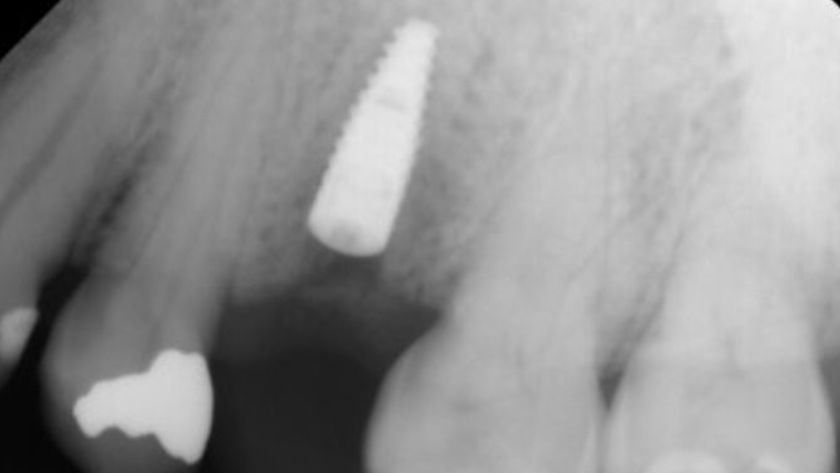

Tooth 13* required extraction in a 54-year-old male patient. The buccal bone was absent. Goal was to restore the site with an implant.